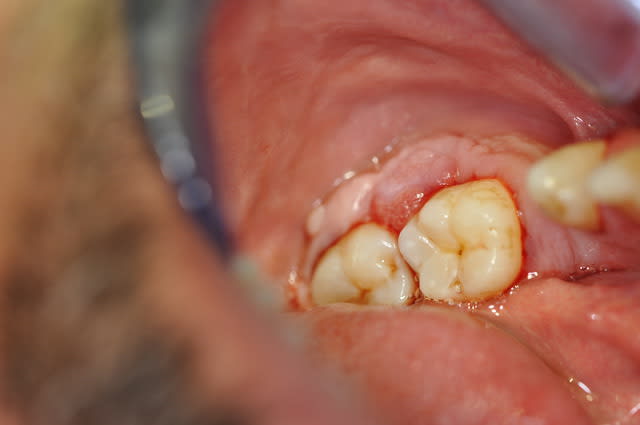

vos avis s il vous plait,

patient qui n a aucune douleur,

du tartre sous gingival mais pas enorme

gencive gonflée avec "des petites boules"

j adresse a un orl ? biopsie ?

58 ans, non fumeur,

pas fait attention a ca au dernier controle, ca semble assez recent

patient qui a deja eu un cancer

et rien d anormal a la radio....

Ca pourrait être une métastase...

Cela me fait penser a un patient que j´ai vu recentment.

Ancien bridge descele.

J´ai fait la biopsie et c´etait inflamatoire.

Même gueule chez un patient que je suis depuis 3-4 ans entre 46-47 avec une poche , une hygiène interdentaire inexistante et une à la brosse limitée. Patient de 80 piges, pas la grande forme (probable anémie latente cf couleur gencives mais ras de prononcé en NFS), revu il y a peu j'ai évoqué mes doutes avec lui, puis ai décidé de ne rien faire compte tenu du bénéfice qu'il retirerait de faire une biopsie et de tomber sur un hypothétique mais très incertain cancer. Sur le long terme pas de changement d'aspect ni de volume, je doute donc fort d'un état cancéreux, pas de saignement spontanées non plus. Je dirais hyperkératose anarchique localisée, réactionnelle à un trauma répété, sans certitude.

Sinon prise de certains médocs augmentant le volume gingival, anti hypertenseur notamment si je me souviens bien. Même si ça colle moyen avec une voussure localisée.